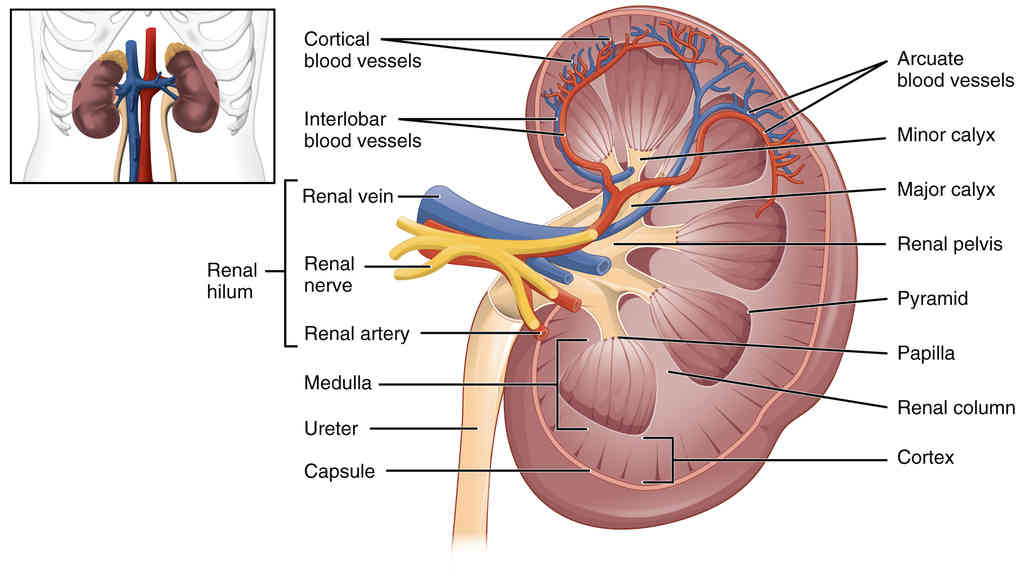

Anatomy, Physiology and Histology

This page is under construction. For now, it is just a resource of the images found in the OpenStax Anatomy and Physiology Handbook. It wil slowly change into a revision tool. Each slide has a number. Use this to refer to the slide. When completed, it will have an unlabelled section, with labelled slides in parallel. On the unlabelled slides, write your answer and use the labelled slide to assess yourself. Keep track by also noting the number on each slide. Improvement at each attempt is important, more so than full marks on a first attempt.